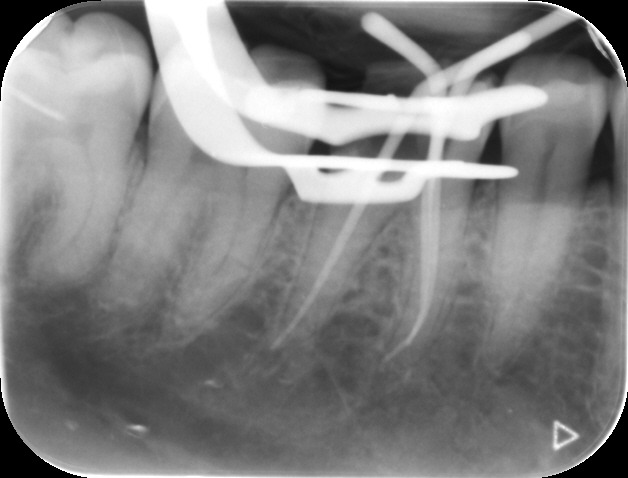

Before commencing the treatment, a local anaesthetic is administered and later a protective non-latex rubber sheet is placed around the tooth to prevent saliva contaminating the tooth and at the same time improves patients comfort.

An access cavity is placed on the surface where the patient bites, to reach the root canals of the tooth. Once all the canals are identified, small files are used to remove the infected pulp.

Files of different sizes are used to eliminate bacteria and infection and to shape the canals. The canals are disinfected thoroughly with irrigants and later the canals will be sealed in 3 dimensions with a special medicament called gutta-percha to prevent reinfection of the tooth and the access cavity will be sealed with a temporary filling.